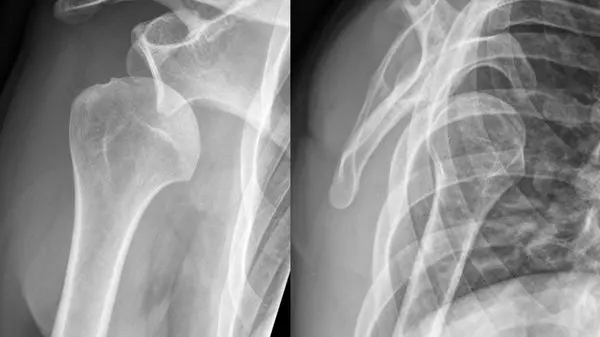

این استاد دانشگاه علوم پزشکی ایران با توجه به شایع ترین تومورهای استخوانی، گفت: کیست های استخوانی لگن که در فضای خالی استخوان ایجاد می شود بسیار شایع است به گونه ای که بیمار در نهایت نیاز به جراحی پیدا می کند.

وی افزود: در موارد اندک کیست استخوانی موجب تضعیف و شکسته شدن استخوان می شود که در این صورت نیز مداخلات جراحی باید انجام شود.